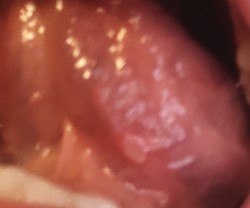

У меня ящур и из-за ящура стоматит